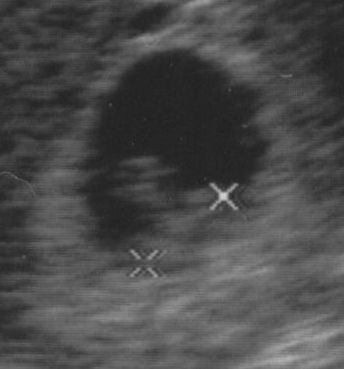

Ottan, a két X között. Kicsit zavar, hogy nem tudom, melyik a feje (ettől még lehetek-e vajon jó anya?), meg remélem, most nem loptam el a lelkét. Csináltathatnék napirajzosan “7 milliméter” feliratú pólót, hmm.

Szerencsére amúgy is be voltam jelentkezve nőgyógyászhoz, nagyon nehéz volt kivárni a negyed hatot, de megérte, biztosított arról, hogy zárva van a méhszáj, van szívhang, megmaradós a baba, csak a méhlepény hülyén tapadt le, és leszakadt belőle egy darab, szedjek utrogestant, ne izguljak. Kaptam fényképet is, amin gyengébbek kedvéért X jelzi a magzat elejét és végét, nagyon helyes egyébként, megegyezésünk értelmében az apjára hasonlít.